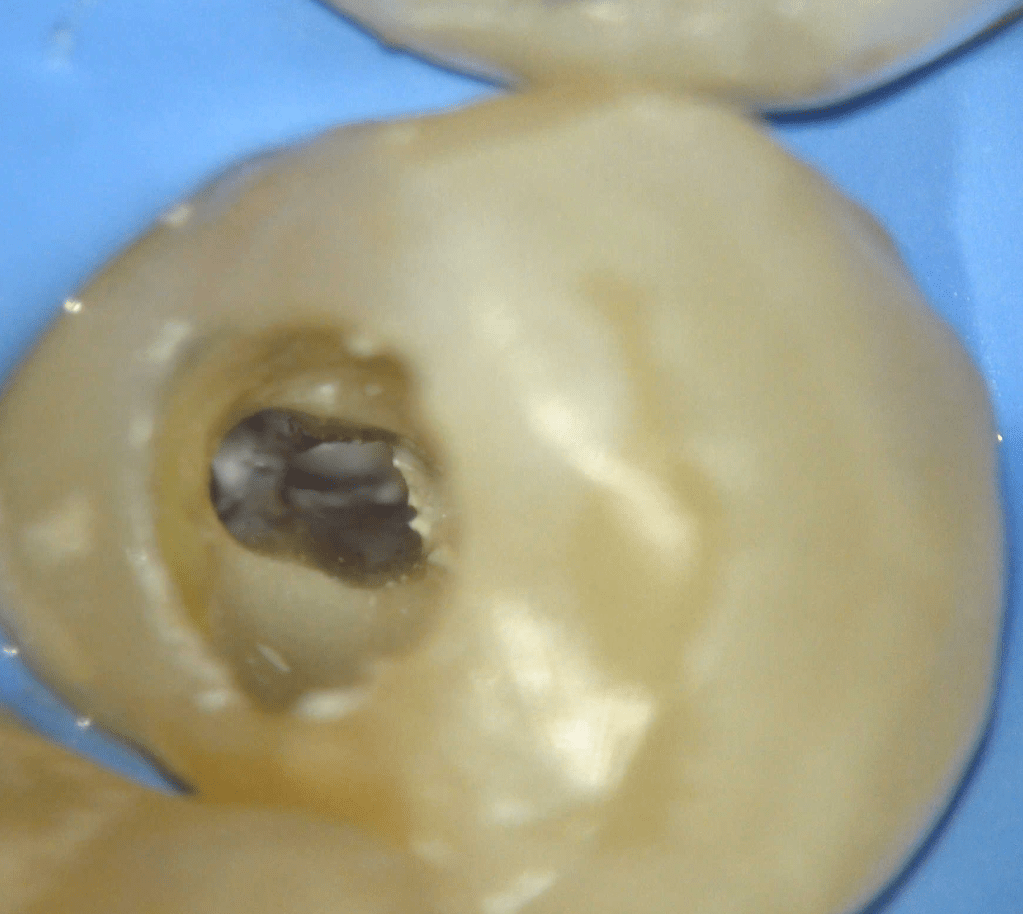

Fisura, remoción amalgama para explorar